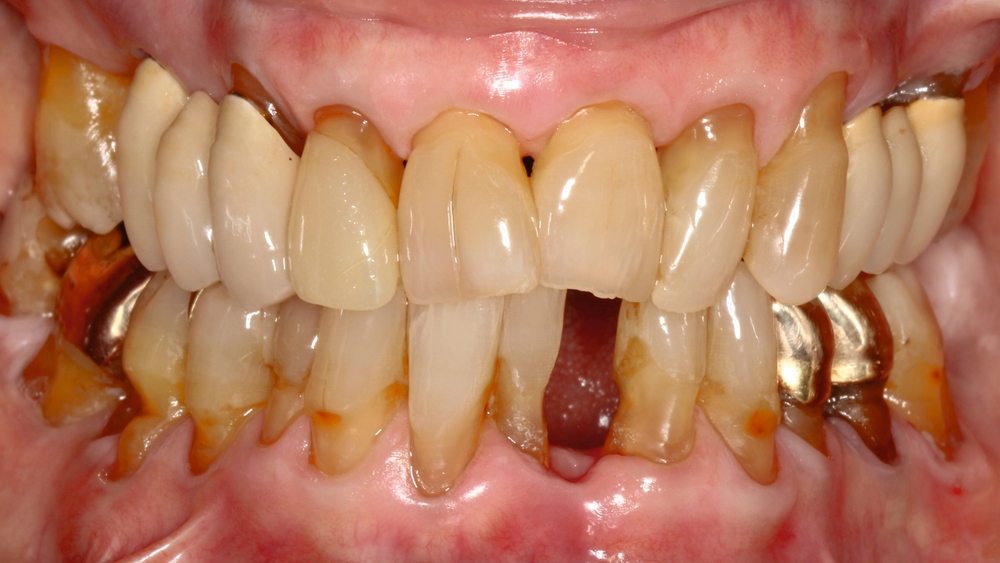

Die Ausarbeitung erfolgte mittels Skalpellen, diamantiert-rotierenden und oszillierenden Instrumenten, rotierenden Schleifscheiben (Sof-Lex XT, 3M Espe), Gummipolierern (Diacomp Plus, EVE) sowie Finierstreifen (Sof-Lex Finierstreifen, 3M Espe) (Abbildungen 11 und 12).

Da die Patientin bereits seit längerer Zeit Interdentalbürstchen verwendete, war das Anwendungs-Training in diesem Fall weniger komplex. Die Verwendung von Interdentalbürstchen und die Teilnahme an der Nachsorge sind in solch einem Fall grundsätzlich jedoch unerlässlich zur Sicherung des Erfolgs. Empfohlen wurde der Patientin aufgrund multipler freiliegender Zahnhälse sowohl oral/vestibulär als auch approximal (Abbildungen 13 und 14) zusätzlich eine Zahnpaste mit einem höheren Fluoridgehalt (Medelmex Duraphat Fluorid 5 mg/g Zahnpasta, CP Gaba).